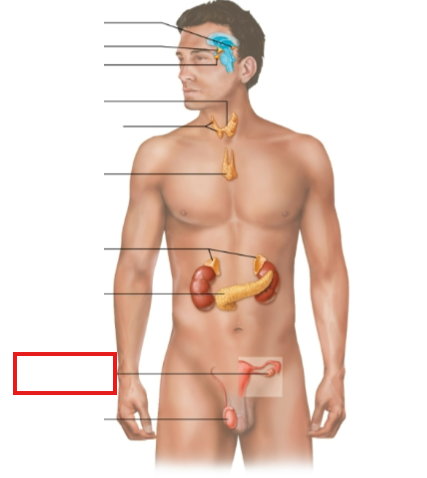

What structure is highlighted?

zona glomerulosa

What structure is highlighted?

zona fasciculata

What structure is highlighted?

zona reticularis

What structure is highlighted?

Capsule

What structure is highlighted?

medulla

What structure is highlighted?

pineal gland

What structure is highlighted?

hypothalamus

What structure is highlighted?

pituitary gland

What structure is highlighted?

thyroid gland

What structure is highlighted?

parathyroid glands

What structure is highlighted?

thymus

What structure is highlighted?

adrenal glands

What structure is highlighted?

pancreas

What structure is highlighted?

ovary (female)

What structure is highlighted?

testes (male)